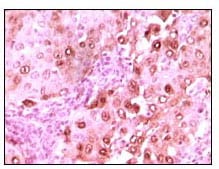

分类: 科研抗体货号: 20054别名: S100A6; 2A9; PRA; 5B10; CABP; CACY应用: IHC反应种属: Human

分类: 科研抗体货号: 20071别名: ECK; EPHA2应用: WB,IHC反应种属: Human